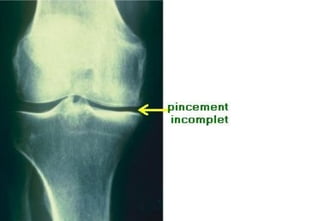

Radiographie standardRadiographie standard ::

IncidencesIncidences ::

-Face debout en extension ou en position de Schuss.Face debout en extension ou en position de Schuss.

-Profil debout en flexion.Profil debout en flexion.

RésultatsRésultats ::

-Pincement de l’interligne articulaire.Pincement de l’interligne articulaire.

-Condensation sous-chondrale du plateau tibial.Condensation sous-chondrale du plateau tibial.

-Géodes sous chondrales (rares).Géodes sous chondrales (rares).

-Ostéophytes (condyles fémoraux plateaux tibiaux, épines tibiales).Ostéophytes (condyles fémoraux plateaux tibiaux, épines tibiales).

Dans la gonarthrose évoluée :Dans la gonarthrose évoluée :

-Enfoncement cupuliforme des plateaux tibiaux.Enfoncement cupuliforme des plateaux tibiaux.

Il n’existe pas de parallélisme radio-clinique.

Arthrose fémoro-tibiale.Arthrose fémoro-tibiale. RadiographiestandardRadiographie standard :: IncidencesIncidences :: -Face debout en extension ou en position de Schuss.Face debout en extension ou en position de Schuss. -Profil debout en flexion.Profil debout en flexion. RésultatsRésultats :: -Pincement de l’interligne articulaire.Pincement de l’interligne articulaire. -Condensation sous-chondrale du plateau tibial.Condensation sous-chondrale du plateau tibial. -Géodes sous chondrales (rares).Géodes sous chondrales (rares). -Ostéophytes (condyles fémoraux plateaux tibiaux, épines tibiales).Ostéophytes (condyles fémoraux plateaux tibiaux, épines tibiales). Dans la gonarthrose évoluée :Dans la gonarthrose évoluée : -Enfoncement cupuliforme des plateaux tibiaux.Enfoncement cupuliforme des plateaux tibiaux. Il n’existe pas de parallélisme radio-clinique.